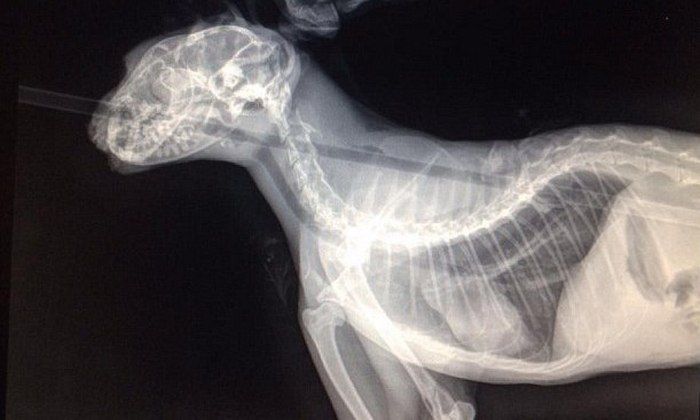

Годовалый кот с примесью сиамской породы немедленно был доставлен в ветеринарную клинику Вашингтона. Ветеринар Джейс Кинг первым делом сделал рентгеновский снимок, чтобы удостовериться, что стрела не задела жизненно важные органы кота.

Стрела прошла в опасной близости от мозга, сердца и легких

Вонзившаяся стрела практически разрезала язык и нёбо Колчана (так прозвали кота), прошла через пищевод и вышла в районе лопаток